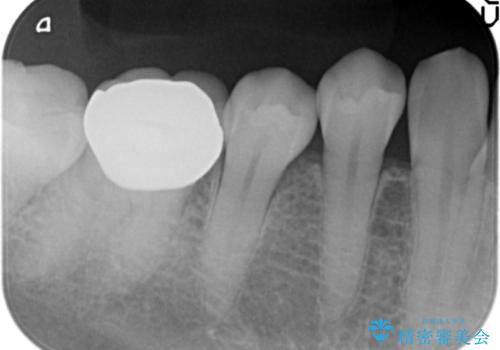

- 笑ったときに目立つ奥歯の銀歯を白くしたいという希望で来院されました。

銀歯を除去し、ジルコニアクラウンによる審美性の回復を計画します。

- 33万円(仮歯・ジルコニアクラウン×3)費用は治療当時の料金となります